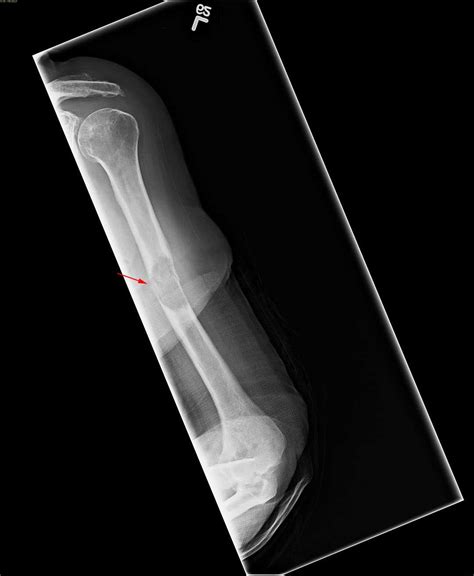

Thyroid cancer typically originates in the follicular or parafollicular cells of the thyroid gland. When it becomes metastatic, it means the cancer has spread beyond the neck to distant sites such as the lungs, bones, or occasionally the liver or brain. The behavior of Metastatic Thyroid Cancer depends largely on the histological subtype—papillary, follicular, medullary, or anaplastic. Most cases involving metastasis are differentiated thyroid cancers, which tend to grow slowly and respond favorably to systemic treatments compared to other forms of malignancy.

• Bone pain or unexplained fractures if the cancer has metastasized to the skeletal system.

Surgery and External Beam Radiation

Surgery may still be utilized to remove large metastatic deposits, especially if they are causing structural damage or compression in the neck or bone. External beam radiation is frequently used to manage localized pain caused by bone metastases or to prevent neurological complications by shrinking tumors near the spinal cord.